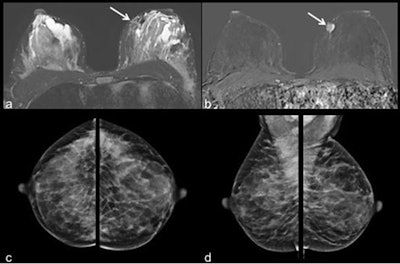

Images of a 40-year-old patient with invasive ductal carcinoma in the left breast at 9 o'clock. The tumor (white arrow) was displayed in the MR images (a = T2 short-tau inversion recovery, b = contrast-enhanced subtraction image). Due to high density of the lactating breast tissue the mass was occult on mammography (c = craniocaudal and d = mediolateral oblique view of both sides). Windowing of MR images was adapted accordingly. Images courtesy of European Radiology.Pregnancy-associated breast cancer

"By using additional postprocessing methods, i.e., supplemental subtraction images, the high background enhancement can be eliminated to facilitate diagnostics for better tumor visualization," they wrote (European Radiology, 18 September 2018). "Ultrasound remains a reliable and readily available diagnostic tool, while interpretations of mammography can be difficult in these patients due to high parenchymal density."